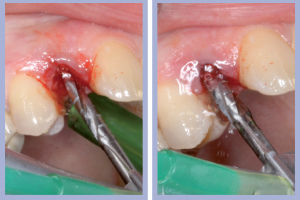

- Figg. 7a, b – Toilette chirurgica

- Figg. 8a, b – Mappatura alveolare tramite sonda parodontale